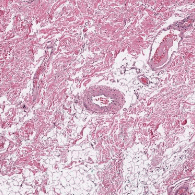

Marking an area on a slide is useful for pointing out an interesting feature, indicating tissue for DNA extraction or training artificial intelligence algorithms. From today, you can annotate slides in Slide Score with easy to use tools.